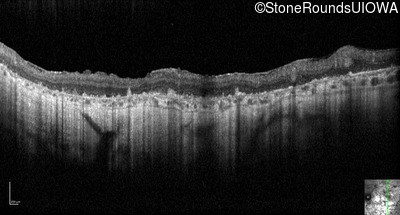

Optical Coherence Tomography - Left - Hand Motion sc

Exemplar / OCT Stack